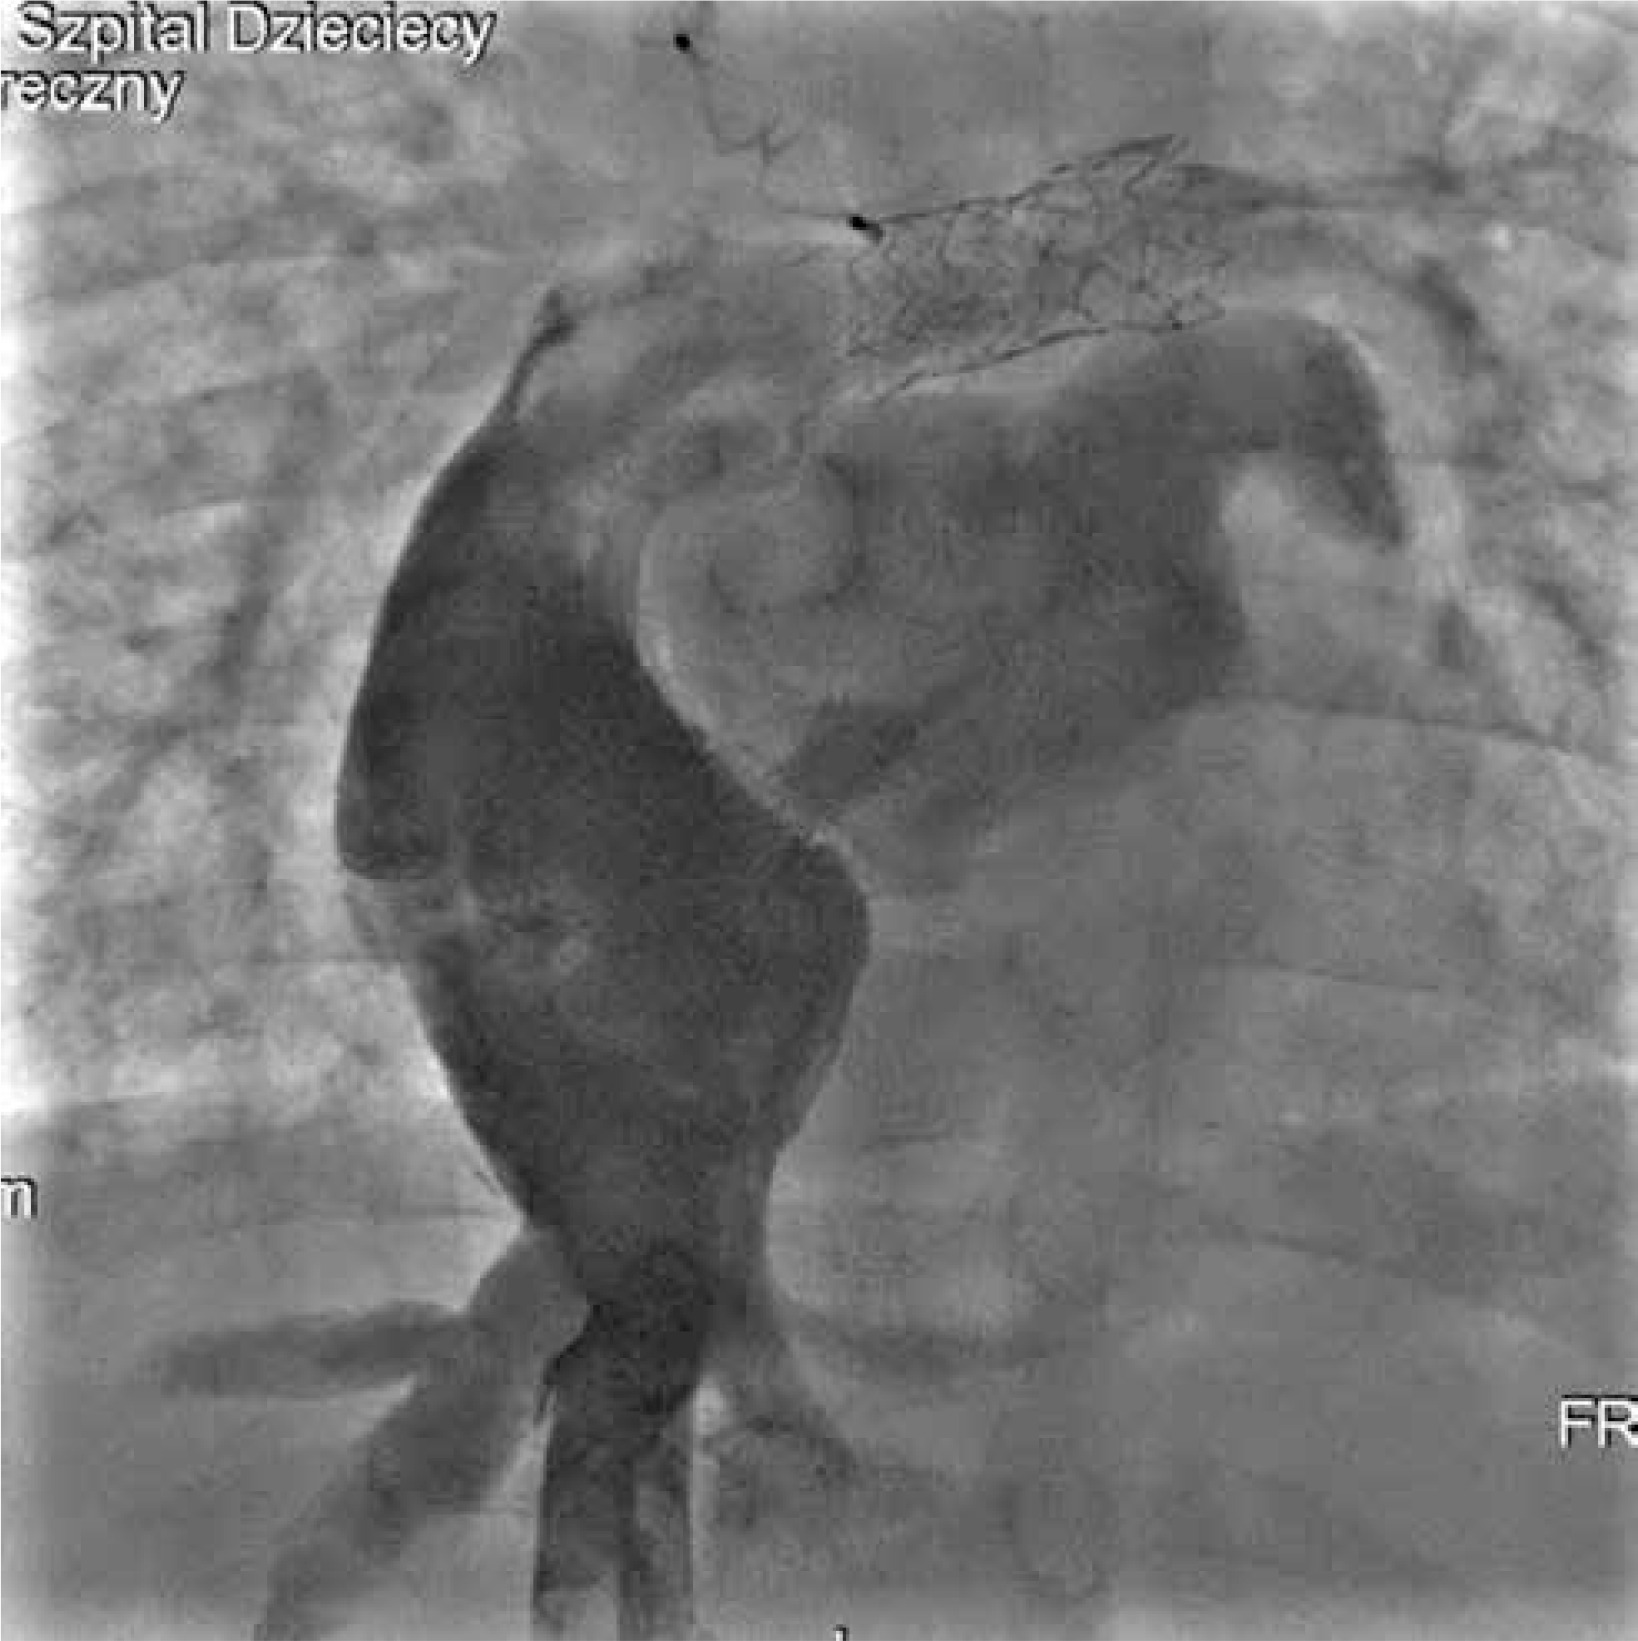

At 5 years of age, given the haemodynamic insufficiency of the Fontan circulation, a multidisciplinary heart team opted for the Hraska procedure with Fontan tunnel revision and tricuspid valve plasty. The procedure was carried out with cardiopulmonary bypass, hypothermia, and cold blood del Nido cardioplegia. The stent was excised from the fenestration, and the Gore-Tex tunnel was removed. The prolapse of the anterior leaflet of the tricuspid valve was corrected with effective valve plasty. A new Gore-Tex tunnel was implanted to direct flow from the IVC to the pulmonary arteries with a 4-mm fenestration. The left brachiocephalic vein was detached from the superior vena cava and anastomosed to the right atrial appendage using a 10-mm Gore-Tex graft to decompress the left jugular angle and thoracic duct into a low-pressure system (Hraska procedure, Figure 6).

The patient recovered uneventfully, with oxygen saturation improving to 90% in the early postoperative period. He was discharged home on the 10th postoperative day with patent Hraska anastomosis (Figure 7) and mild systolic and diastolic right ventricular dysfunction on pharmacologic treatment.

Figure 7

Echocardiographic picture of patent Hraska anastomosis between the left brachio-cephalic (innominate) vein and right atrial appendage. The colour Doppler flow through the 8 mm reinforced polytetrafluoroethylene (Gore-Tex) vessel anastomosis is visible